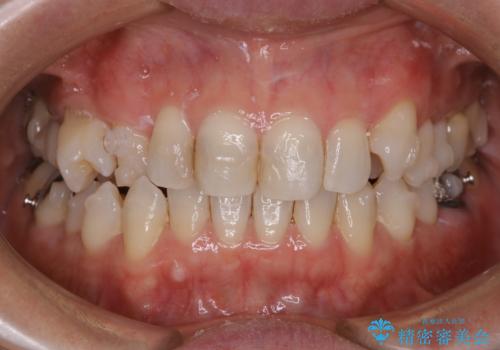

90度捻じれてしまい、完全にはみ出している歯を抜かずにインビザラインで治す。一般治療もできる精密審美会だからこその治療

- 右上の小臼歯が二本とも90度捻じれてしまっており、奥歯の噛み合わせに問題が生じていました。

歯を抜いてワイヤー治療を行うという選択肢もありましたが、

奥歯の被せ物の形を適切にすることで非抜歯でも治療が可能であると判断し、

非抜歯、インビザラインでによるマウスピース矯正治療を行うことにいたしました。

今回は右上の奥歯に入っていた銀歯の形が悪く、そのせいで歯を並べるスペースが足りない状態でした。

右上の歯の被せ物を作りなおし、適切な歯の大きさに代えてあげることによってスペースを作りました。

また、それだけではスペースが足りない為右上の奥歯は遠心移動を行っています。